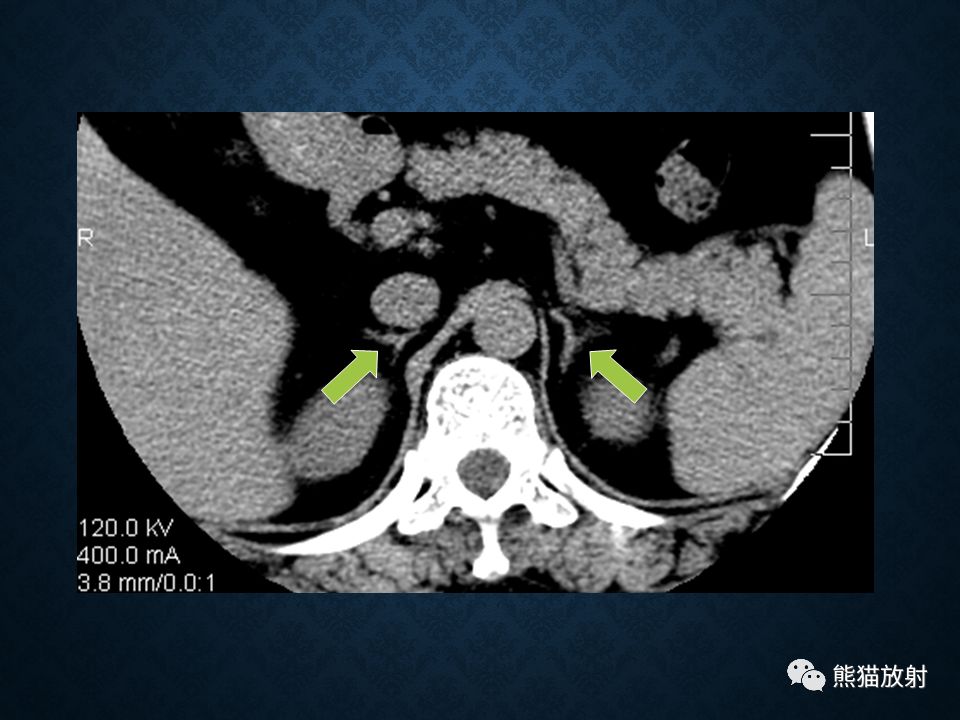

肾上腺常见肿瘤影像诊断

>腺瘤:临床表现决定于肿瘤的发生年龄,与 Cushing腺瘤表现相同,但无对侧萎缩改变

>皮质癌:约占30%

>先天性肾上腺增生:双侧肾上腺腺体显著弥漫性增大,程度常明显超过 Cushing综合征的皮质增生